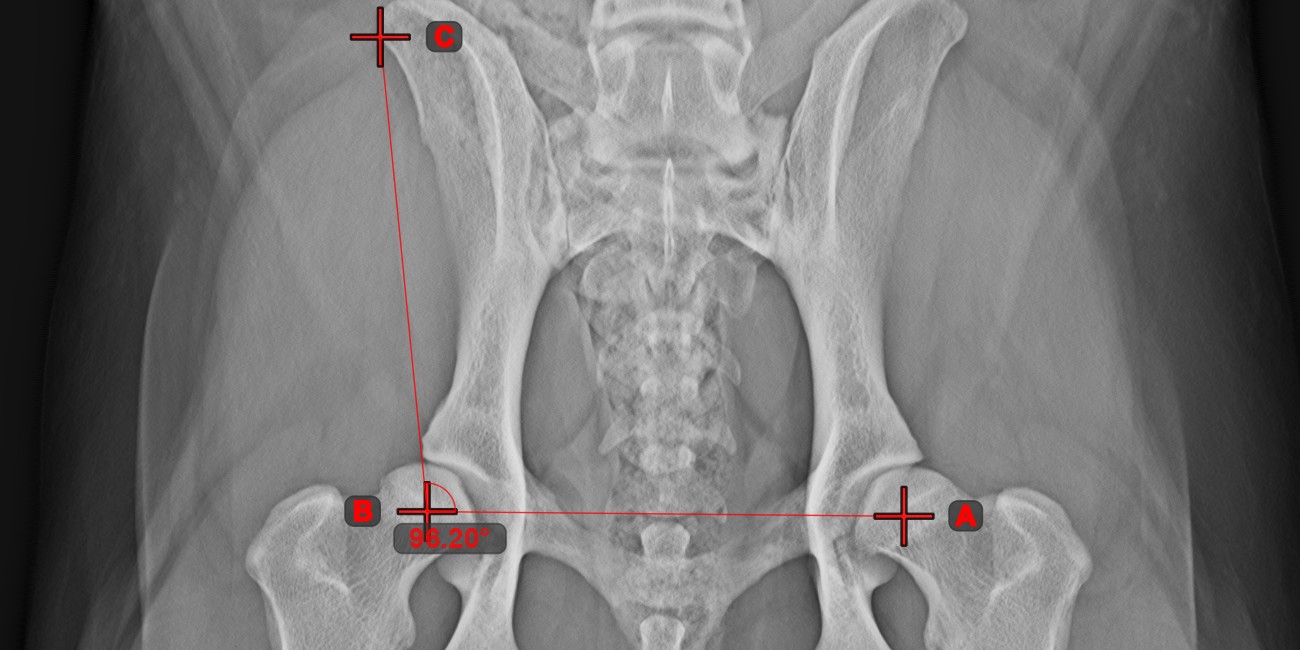

Angle of Lines¶

Select the tool from the left toolbar and assign it to one of the available mouse buttons. Start by selecting the first line from the ones already drawn on the scene, or place the start and end points to create the line. Follow the same steps for the second line of the measurement. The angle between the two lines will be automatically calculated.

Modify the start and end points of both lines by using the Select/Move Item

tool. The angle between the two lines will be automatically recalculated.

Information

If two lines do not intersect directly, the angle of their extended projections on the scene will be calculated.

Angle from 3 Points¶

The Angle from 3 Points

tool is a simple and effective way to calculate an angle from just three points.

Start by selecting the tool from the left toolbar and assign it to one of the available mouse buttons. Place the start point of the initial side, the vertex, and the end point of the terminal side of the angle, or select the points from the scene. The sides of the angle will be automatically constructed, thus calculating the angle between the lines.